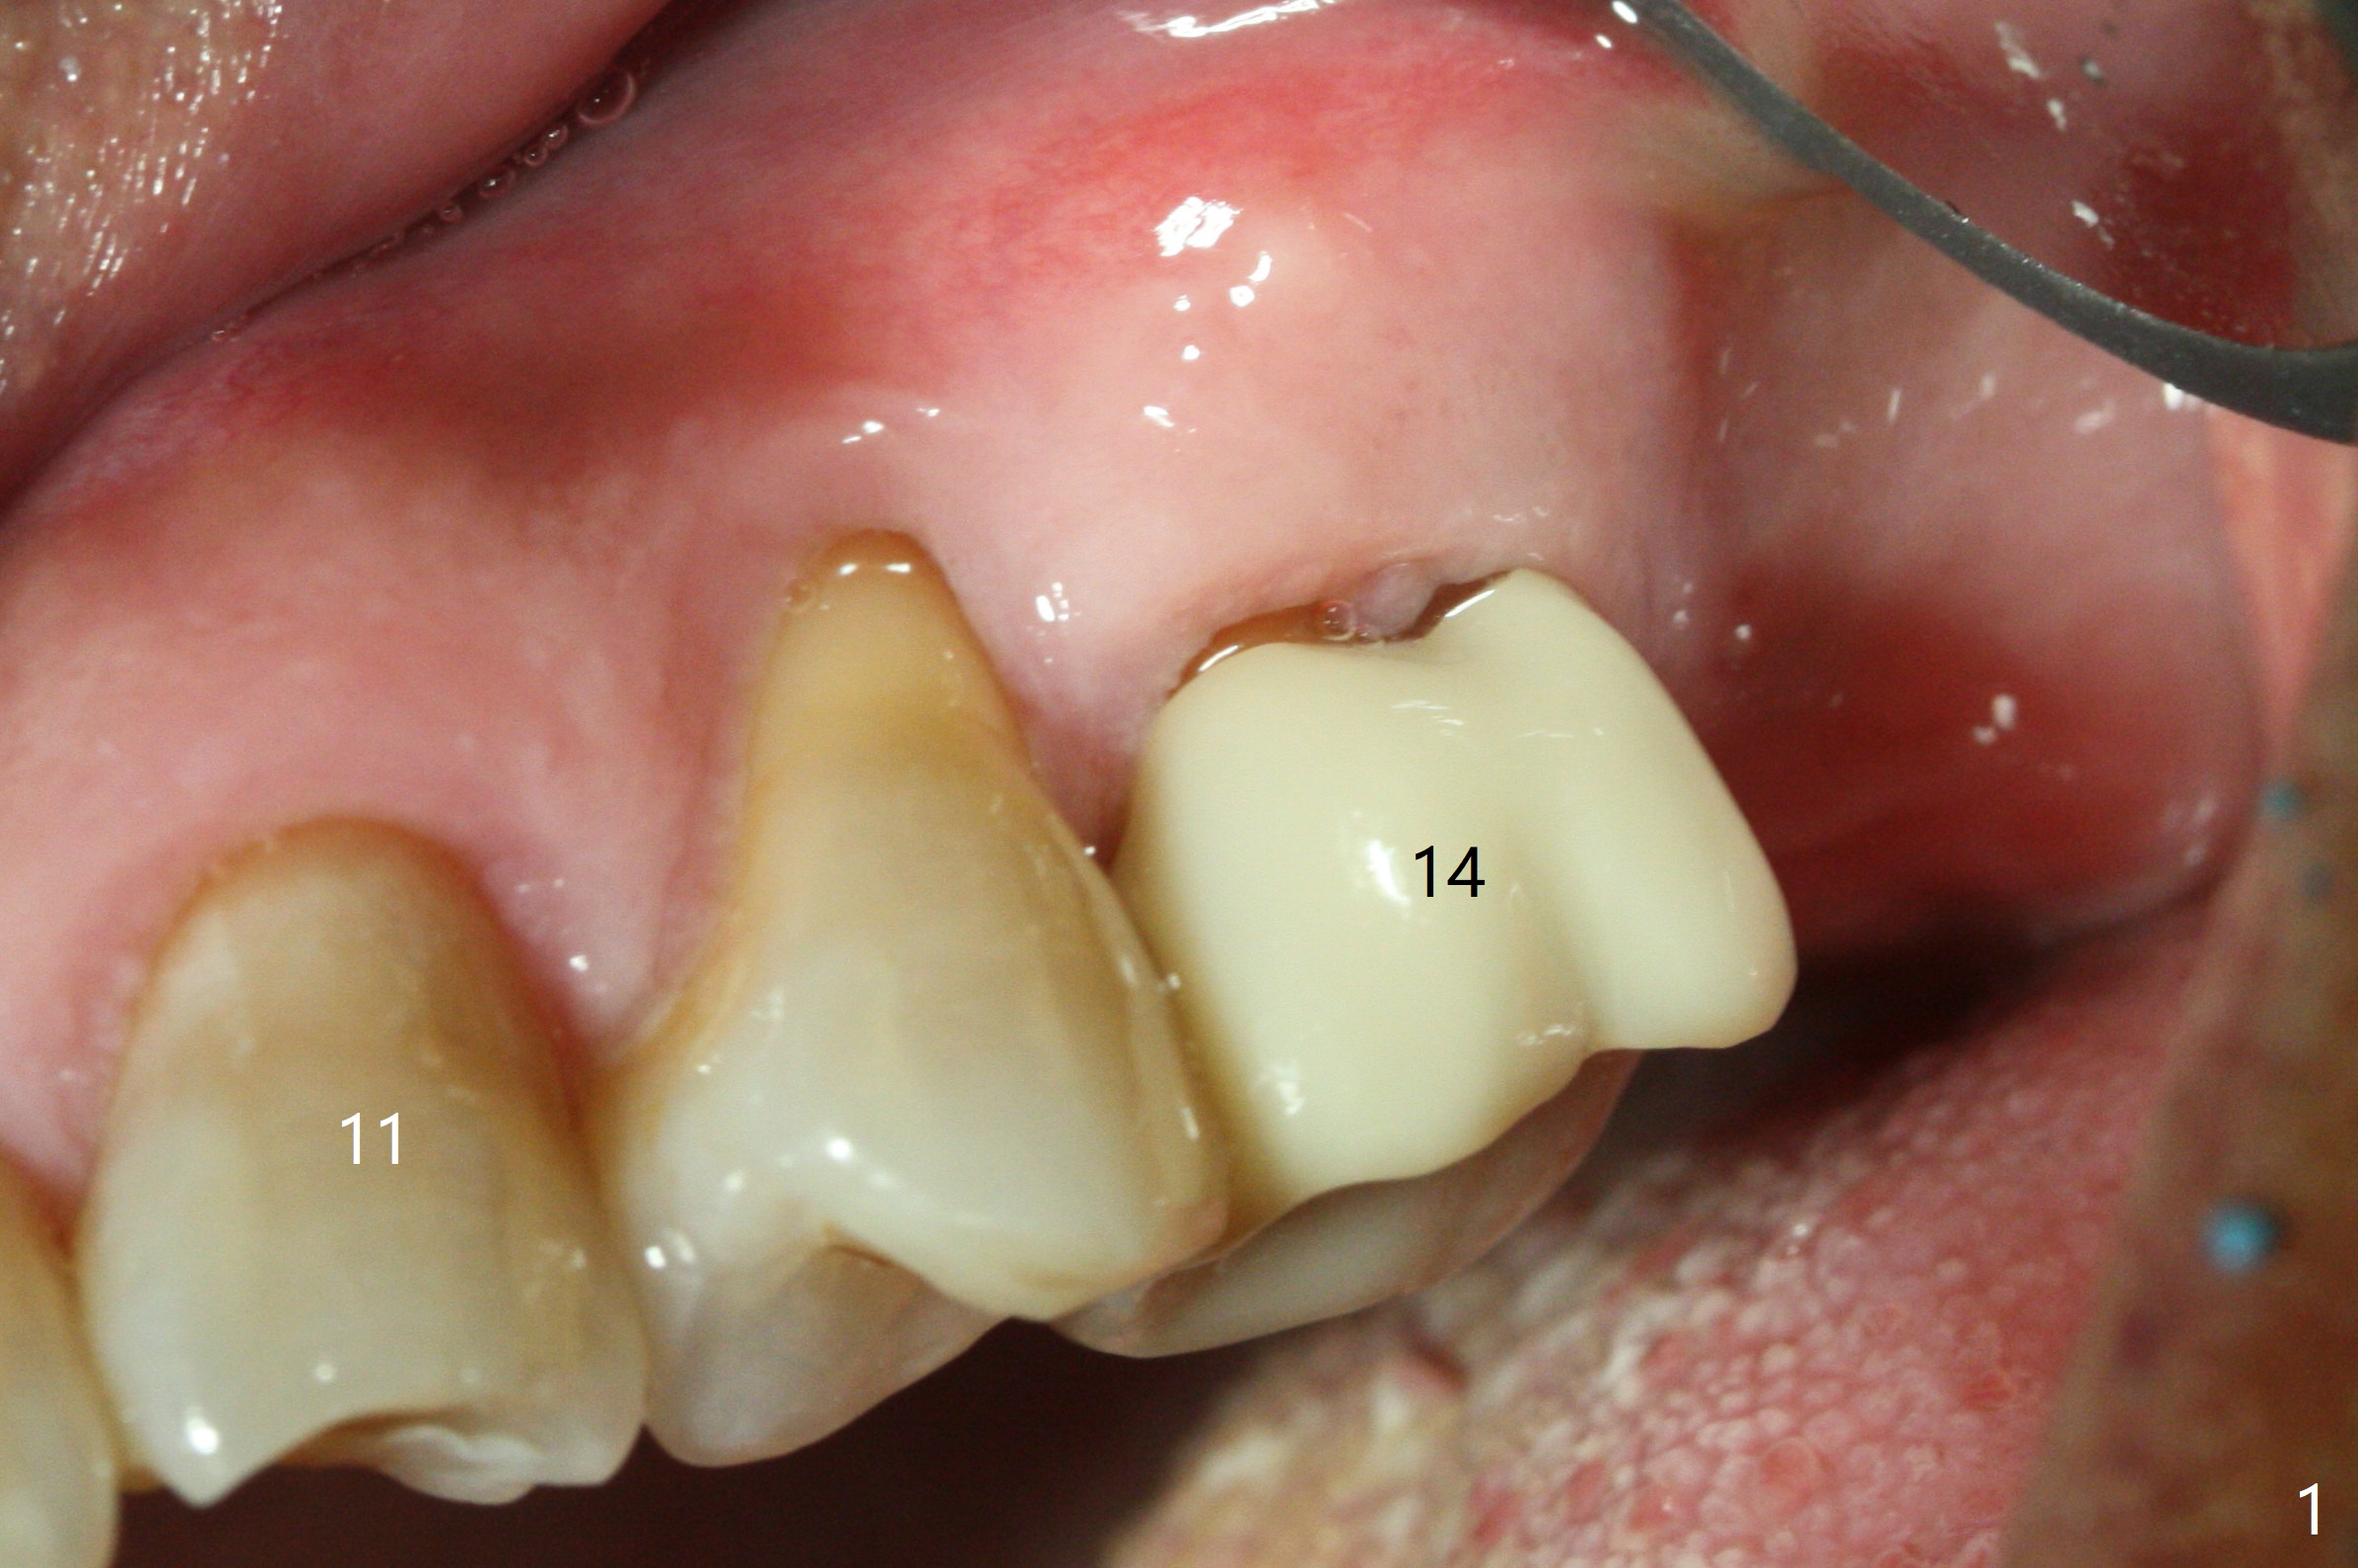

After extraction of the tooth #14 (Fig.1) and removal of granulation tissue associated with a distal fistula, a 1.6 mm drill is used to initiate osteotomy in the septum for 9 mm, followed by insertion of a 7 mm long parallel pin (Fig.2). The length of the subsequential osteotomy is 11 mm until 4.8 mm in diameter (overprep as will be shown below). The bone is hard so that sinus lift fails with 4.8 mm Magic Expander. Since a 5x9 mm dummy implant is placed with stability, a definitive implant with the same dimension is chosen with >50 Ncm (Fig.3,4). Prior to and after abutment placement, Vera graft is placed (*). The provisional perforates with loose abutment 3.5 months postop. A 6x4 mm healing abutment is placed. Osteointegration occurs 4 months postop (Fig.5,6).